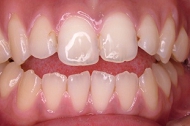

前歯1本だけが出ています、矯正で治りますか?

(23歳/女性)↓

概要・担当医コメント:

前歯の唇側傾斜/マルチブラケット装置/非抜歯

動的治療期間15ヶ月(15回)/費用概算:60万円.

歯列アーチの形態修正に必要なスペースを微量のエナメル質の研磨により創生し,当初の計画通りに歯を移動させました.